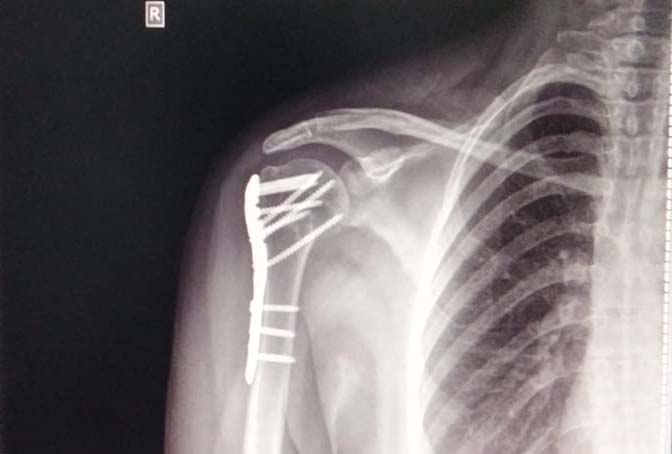

Trauma Fracture